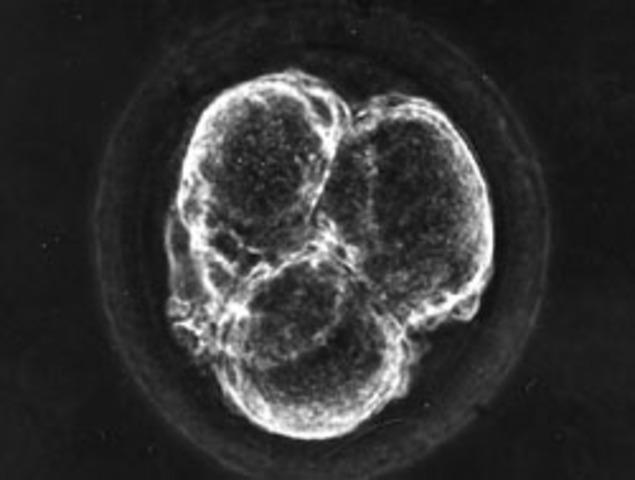

It is a short period comparing to the next stages. The fertilized egg will start to divide very rapidly and it will migrate from the Fallopian tube to the uterus. The fertilized egg or the blastocyst will be implanted in the uterus. The main purpose of this stage , to generate a massive number of cells. For instance, some cell will be forming the placenta and the umbilical cord. Placenta is the main entrance for the nutrition. Umbilical cord is the main exit of the waste material. This stage ta

Fertlization to 2 weeks